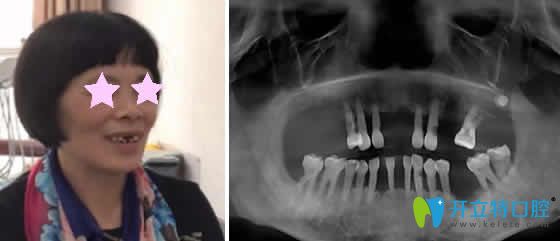

老媽在重慶華諾世口腔做即刻種植牙的個(gè)人經(jīng)歷分享

即刻種植牙重慶口腔發(fā)布時(shí)間: 2023-02-05

仔細(xì)把重慶口腔排名中口碑較好的做了對(duì)比后,決定帶老媽去華諾世口腔種牙,今天在這里分享下老媽在重慶華諾世口腔做即刻種植牙的個(gè)人經(jīng)歷,讓大家知道其實(shí)種植牙價(jià)格真不貴!